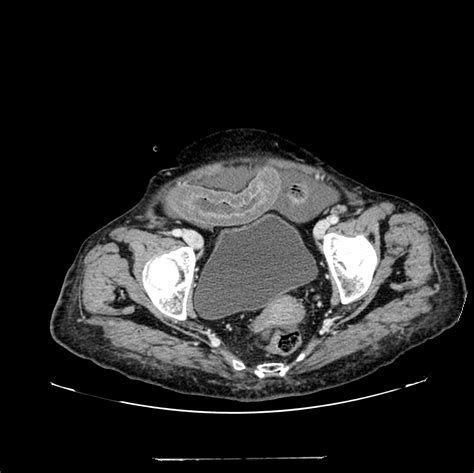

Suspicion is an important part of the diagnostic process. Doctors use their clinical experience, along with information from the patient, to form a hypothesis. They then order tests and investigations to either confirm or refute this hypothesis. For abdominal pain, if ischemia is suspected, the doctor may order imaging tests like a CT scan or an angiogram to visualize the blood vessels in the abdomen. They might also order blood tests to check for signs of tissue damage. The level of suspicion affects the urgency and type of diagnostic tests performed. If the doctor strongly suspects ischemia, they will likely order tests immediately. The correct use of ICD-10 codes is really important because it prompts the doctor to think about the possibility of ischemia and helps guide them toward the appropriate tests. Accurate coding improves the chances of a correct and timely diagnosis, which is really important for a condition like ischemia. So, the next time your doctor is asking you a bunch of questions, remember that their suspicions, combined with your detailed descriptions, are the first steps toward getting you the right diagnosis and treatment.